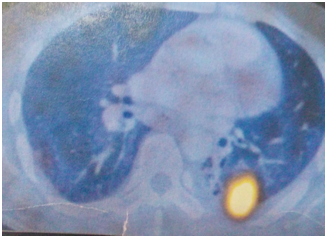

A 45year old male patient presented with a history of dyspnoea and cough since 8months. The patient was well built and nourished. His vitals were stable. Plain radiograph of chest, CT thorax was normal. Diagnostic bronchoscopic was done, the bronchial brushing was taken and was found to be positive for pulmonay tuberculosis (PTB). The patient was started on anti-tubercular therapy (ATT). He completed 6months of therapy and there was marginal reduction in the symptoms. A repeat CT thorax was done showing pleural thickening with hyperinflated left lung and bronchiectatic changes multiple patchy areas of consolidation in bilateral lungs. A CT guided biopsy was taken from the Left pleural thickening. The microscopy showed a mixed feature of spindle cells interlaced with plasma cells and lymphocytes. Immunohistochemistry (IHC) showed positivity for smooth muscle actin and vimentin and ki-67 index was 12%, the ALK was negative confirming the diagnosis of IMT. PET-CT was done which also confirmed the findings as in the CT thorax, with hyper-metabolic uptake in the left pleura and bilateral supraclavicular areas. The patient was continued on ATT till 9months, as well as started on pulsed dose steroid therapy starting dose at Oral prednisolone 30mg was started for 10days and tapered with 5mg decremental doses over a period of 4weeks (Figure 1–3).

Figure 2 Proliferation of regular myofibroblasts mixed with lymphocytes and plasma cells (high magnification).

The biopsy is necessary to confirm the diagnosis, which usually shows a combination of inflammatory cells and mesenchymal cells which mainly is the plasma cells, histiocytes, lymphocytes and spindle cells Pettinato et al.,5 has described IFT histologically to be a an inflammatory cells with proliferative myofibroblasts and fibroblasts, with IHC positive for vimentin and smooth muscle actin.6 The IMT can invade blood vessels but a rare occurrence, as it infiltrates the lung with the inflammatory cells, it is very difficult to differentiate as the normal lung architecture gets distorted. The imaging studies done at baseline was normal, but a repeat CT thorax was done showing pleural thickening with hyper inflated left lung and bronchiectatic changes multiple patchy areas of consolidation in bilateral lungs. PET-CT confirmed the findings with hyper-metabolic uptake in the bilateral supraclavicular areas. In our case the biopsy of the pleural thickening showed mixed areas of spindle cells interlaced with plasma cells and lymphocytes. IHC positive for smooth muscle actin, vimentin and ALK negative, confirming IMT.